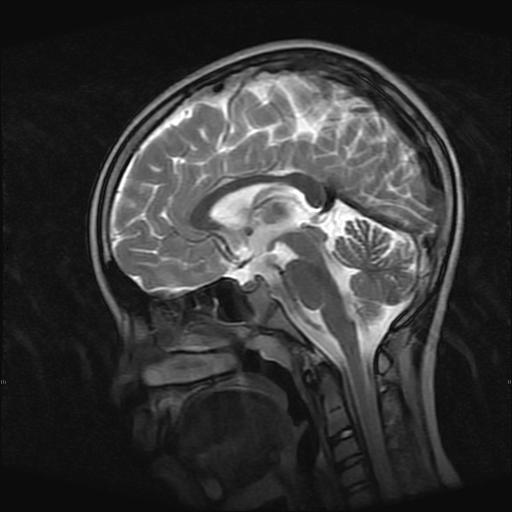

9岁女孩,三岁时诊断为癫痫,一直服丙戊酸钠,现患者一般情况良好,家长复查核磁片,看能否停药..

未见异常信号灶.

未发现异常信号。